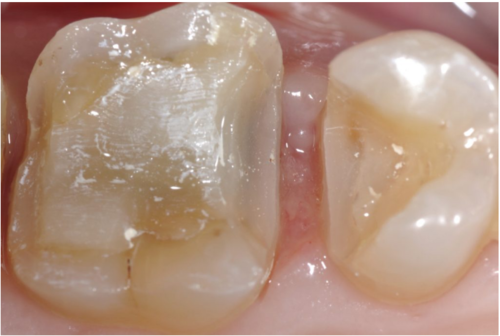

图3 骨板及位于颊侧的下牙槽神经(尚未分离)

在手术中进行翻瓣以暴露第三磨牙时,遇到了一些阻力。经过仔细检查,发现一根与骨膜瓣粘连的绳索状结构。将其轻轻分离后,确认该结构为下牙槽神经。该神经在距离口腔皮质骨外侧1.5厘米处穿出,且没有骨组织覆盖,随后重新进入下颌骨。

下牙槽神经被提起后,骨板上的凹槽显露出来。进一步对CT图像进行检查,确认下颌神经从颊侧骨板穿出,并且在神经与囊肿之间存在正常骨质,下颌神经在一个开放的通道内自由移动。